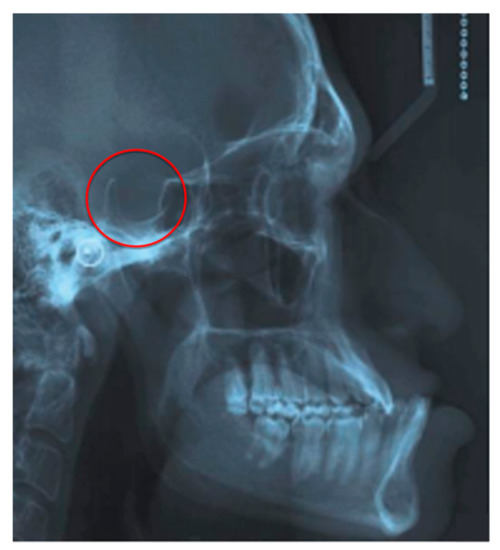

- Nagaraj, T.; Shruthi, R.; James, L.; Keerthi, I.; Balraj, L.; Goswami, R.D. The size and morphology of sella turcica: A lateral cephalometric study. Radiol. Pathol. Surg. 2015, 1, 3–7. [Google Scholar] [CrossRef]

| Clicks and TMJ pains | Dental and gnatologic evaluation, radiographic deepening with RM | Functional treatment with gymnastics for the temporomandibular joint or application of a customized bite The BruxApp app can be adopted under the control of the dentist to monitor and correct incorrect or flawed positions maintained during the day by the patient and to guide postural re-education |